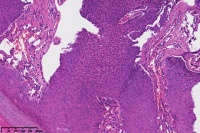

汗孔瘤?

性别

女

年龄

50岁

足底丘疹

汗孔瘤。